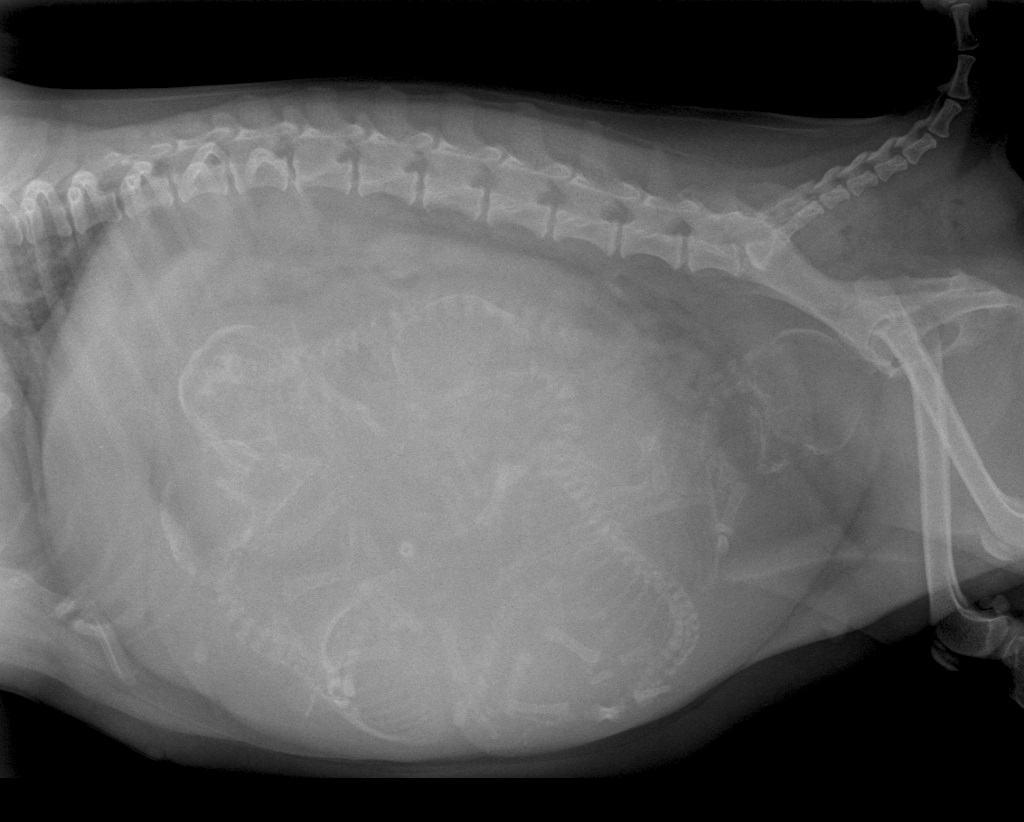

De bevalling stagneerde en het was voor ons zaak om snel te bepalen wat daar de oorzaak van was. Weeรซnzwakte? Of lag er een pup verkeerd? Of was de pup gewoon te groot voor het geboortekanaal? Omdat we weten dat chihuahua-pups nogal eens een te groot hoofdje hebben voor het bekken van de moeder besloten we direct een rรถntgenfoto van Luna's buik te maken. Op deze foto was goed te zien dat er inderdaad een pup met een fors koppie voor de bekkeningang vastliep en besloten we direct een keizersnede uit te voeren. Er werden vier mooie pups geboren, drie teefjes en een reu. Inmiddels zijn we anderhalve week verder en doen moeder en pups het fantastisch!

Rรถntgenfoto van Luna's buik: zoek de vier kopjes